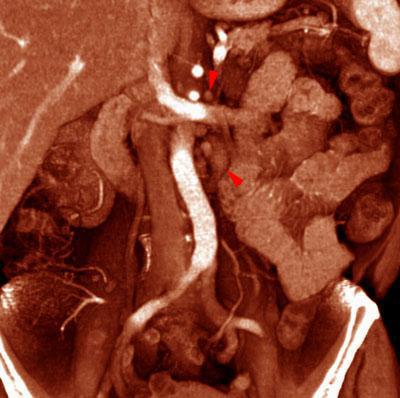

VR seccional. Visión coronal anterior. TC contrastado en fase venosa mostrando adenopatías retroperitoneales en cadena paraaórtica izquierda (puntas de flecha)